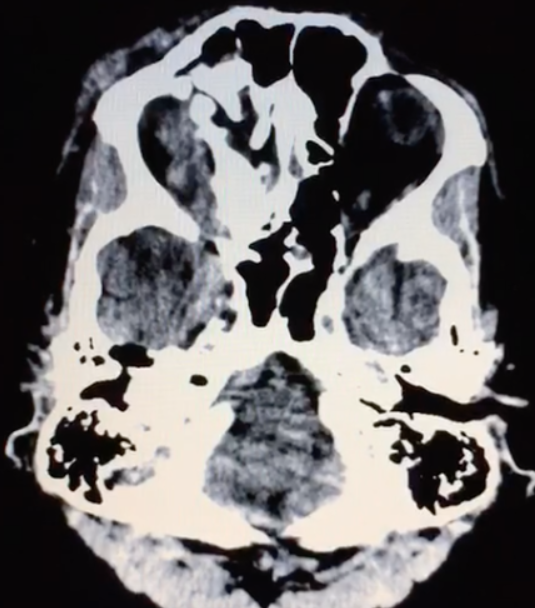

- Tomografia de crânio estrutura captante com a invasão de contraste. Ausência de coleção purulenta e presença de lesão em topografia de seio cavernoso e evidência da veia oftálmica superior. Além disso, a TC mostra sinais de traumatismo prévio (fratura frontal).

As fístulas arteriovenosas (FAVs) da região do seio cavernoso (SC) são lesões raras e difíceis de diagnosticar. Os principais sinais e sintomas são proptose, hiperemia conjuntival, quemose, paralisia dos III, IV, V e VI nervos cranianos, ptose palpebral, glaucoma, redução da acuidade visual e cefaleia. Nas fístulas carótido-cavernosa existe um defeito na parede da artéria carótida interna (ACI) que a comunica diretamente com o SC e, em consequência, um shunt arteriovenoso de grande volume. Na TC podemos identificar dilatação ou trombose da veia oftálmica superior (VOS), proptose, contrastação precoce do SC, espessamento da musculatura extraocular e edema da gordura periorbitária3.

As FCC diretas apresentam na maioria dos casos um alto débito ao contrário das FCC indiretas que em termos hemodinâmicos são de baixo débito. Etiologicamente as primeiras são traumáticas em cerca de 75% dos casos podendo, no entanto, ocorrer espontaneamente. As FCC indiretas são geralmente espontâneas, ocorrendo classicamente em mulheres pós-menopáusicas ou em grávidas. O diagnóstico é efetuado pela clínica e por Tomografia Computadorizada de crânio e/ou Ressonância Magnética Nuclear das Órbitas, onde o sinal mais específico é a dilatação da veia oftálmica superior. No entanto, o diagnóstico definitivo, a caracterização da fístula e o planejamento do tratamento endovascular só são possíveis com a angiografia cerebral6.